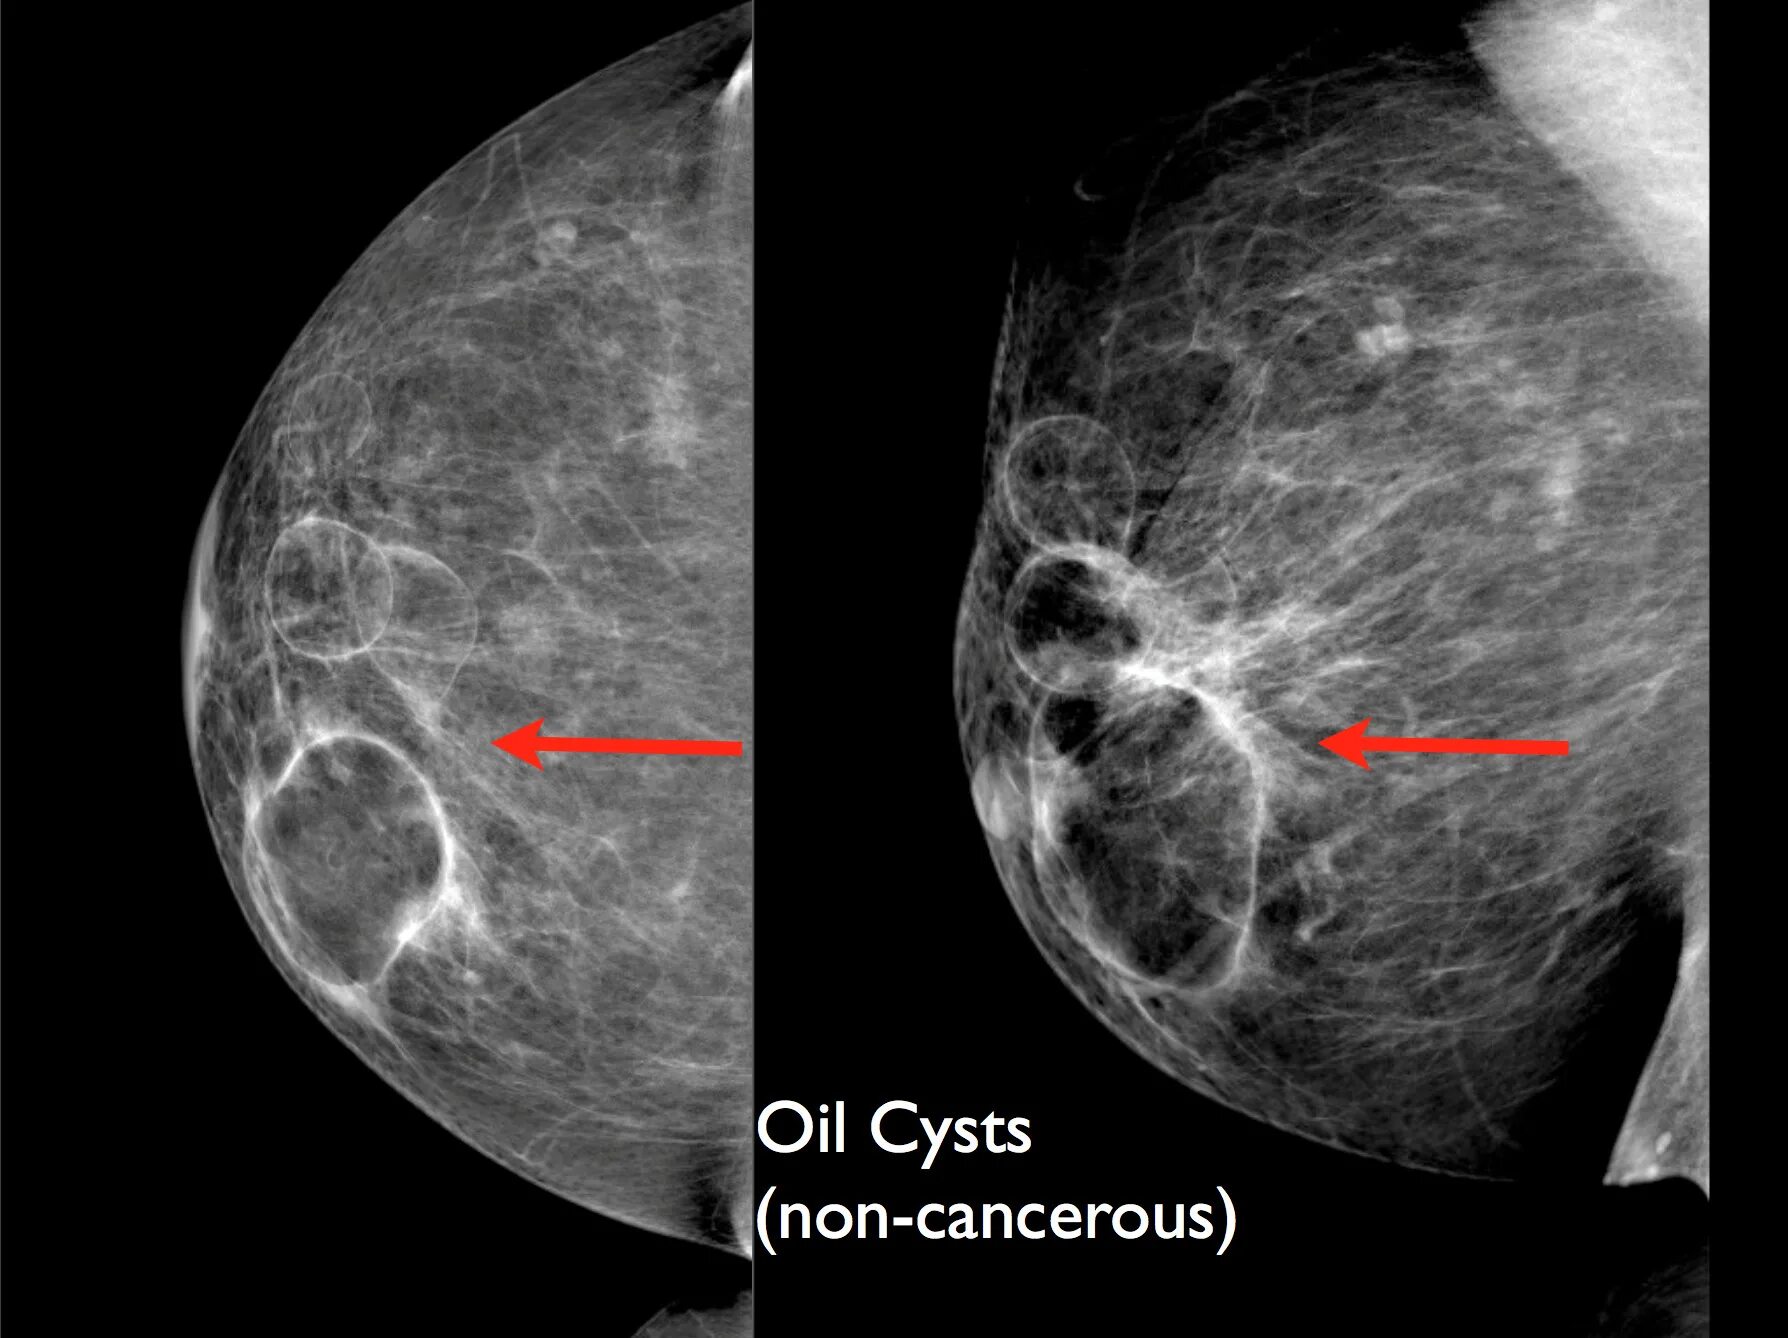

Фиброз грудных